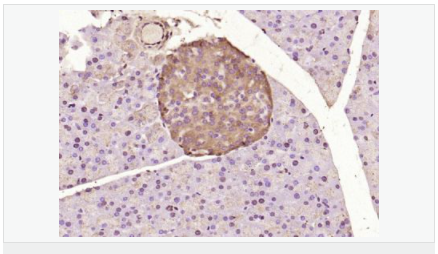

| 產(chǎn)品應用 | WB=1:500-2000 ELISA=1:5000-10000 IHC-P=1:100-500 IHC-F=1:100-500 Flow-Cyt=1μg /test IF=1:100-500 (石蠟切片需做抗原修復) not yet tested in other applications. optimal dilutions/concentrations should be determined by the end user. |

| 細胞定位 | 細胞核 細胞漿 |

| 產(chǎn)品介紹 | ATF6 is a transcription factor that acts during endoplasmic reticulum stress by activating unfolded protein response target genes. It binds DNA on the 5'-CCAC[GA]-3'half of the ER stress response element (ERSE) (5'-CCAAT-N(9)-CCAC[GA]-3') and of ERSE II (5'-ATTGG-N-CCACG-3'). Binding to ERSE requires binding of NF-Y to ERSE. ATF6 could also be involved in activation of transcription by the serum response factor. ATF6 exists as a homodimer and heterodimer with ATF6 beta. The dimer interacts with the nuclear transcription factor Y (NF-Y) trimer through direct binding to NF-Y subunit C (NF-YC). It also interacts with the transcription factors GTF2I, YY1 and SRF. Under ER stress the cleaved N-terminal cytoplasmic domain translocates into the nucleus. The basic domain of ATF6 functions as a nuclear localization signal and the basic leucine zipper domain is sufficient for association with the NF-Y trimer and binding to ERSE. During the unfolded protein response an approximately 50 kDa fragment containing the cytoplasmic transcription factor domain is released by proteolysis. The cleavage seems to be performed sequentially by site 1 and site 2 proteases. ATF6 is N glycosylated, phosphorylated in vitro by MAPK14/P38MAPK and belongs to the bZIP family. Function: Transcription factor that acts during endoplasmic reticulum stress by activating unfolded protein response target genes. Binds DNA on the 5'-CCAC[GA]-3'half of the ER stress response element (ERSE) (5'-CCAAT-N(9)-CCAC[GA]-3') and of ERSE II (5'-ATTGG-N-CCACG-3'). Binding to ERSE requires binding of NF-Y to ERSE. Could also be involved in activation of transcription by the serum response factor. Subunit: Homodimer and heterodimer with ATF6-beta. The dimer interacts with the nuclear transcription factor Y (NF-Y) trimer through direct binding to NF-Y subunit C (NF-YC). Interacts also with the transcription factors GTF2I, YY1 and SRF. Subcellular Location: Endoplasmic reticulum membrane; Single-pass type II membrane protein. Processed cyclic AMP-dependent transcription factor ATF-6 alpha: Nucleus. Note=Under ER stress the cleaved N-terminal cytoplasmic domain translocates into the nucleus. Tissue Specificity: Ubiquitous. Post-translational modifications: During unfolded protein response an approximative 50 kDa fragment containing the cytoplasmic transcription factor domain is released by proteolysis. The cleavage seems to be performed sequentially by site-1 and site-2 proteases. N-glycosylated. The glycosylation status may serve as a sensor for ER homeostasis, resulting in ATF6 activation to trigger the unfolded protein response (UPR). Phosphorylated in vitro by MAPK14/P38MAPK. Similarity: Belongs to the bZIP family. ATF subfamily. Contains 1 bZIP (basic-leucine zipper) domain. SWISS: P18850 Gene ID: 22926 Database links: Entrez Gene: 22926 Human Entrez Gene: 226641 Mouse Omim: 605537 Human SwissProt: P18850 Human Unigene: 492740 Human Important Note: This product as supplied is intended for research use only, not for use in human, therapeutic or diagnostic applications. |